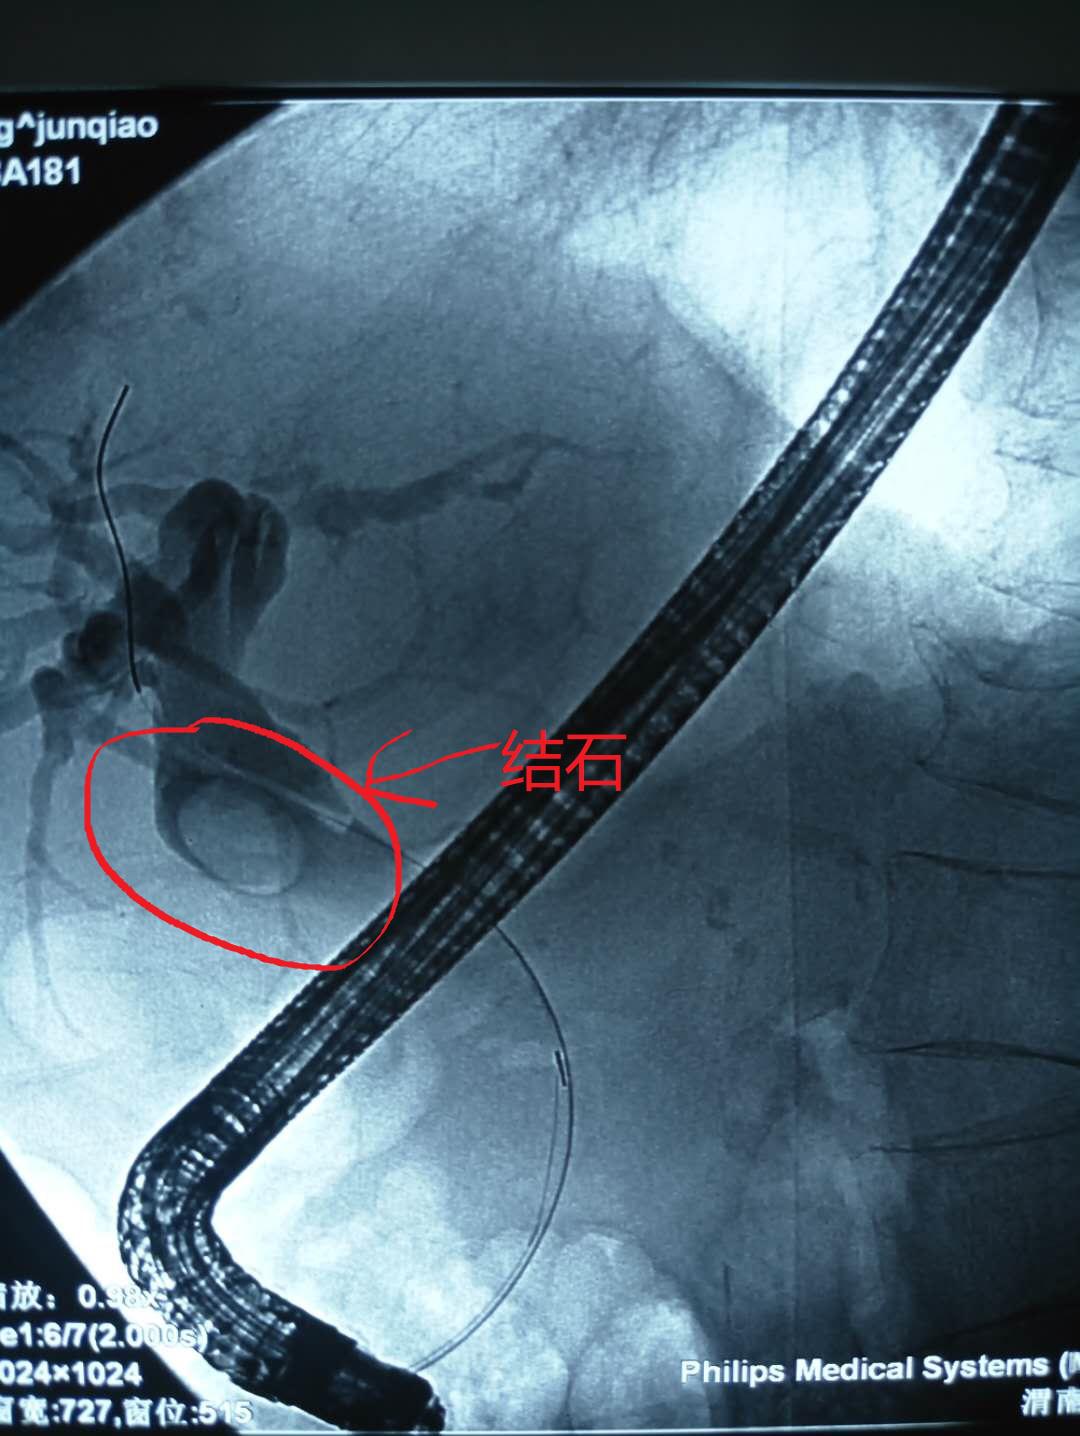

患者梁某,女性,87岁,因“腹痛2月”收住消化内科,诊断为胆总管结石、化脓性胆管炎、冠心病、心房纤颤、高血压2级、脑梗塞、电解质紊乱(低钾血症)。患者入院后伴有发热,最高体温41℃,急性化脓性胆管炎症状急剧加重,生命危在旦夕,一分一秒都在与生命赛跑。以往唯一生还的机会就是开刀手术,但是这位高龄患者很难下手术台;如果保守治疗唯一的结果就是因感染性休克及严重合并症而死亡。就在此时,消化内科主任王宇晖、主治医师曹鹏、白欣与手麻科雷育华主治医师、介入科何彤副主任多学科联合会诊,根据病情迅速制定了最佳手术方案,那就是为患者实行ERCP胆道取石。手麻科迅速为患者实行插管麻醉,密切监护生命体征,介入科配合,由曹鹏医生快速将胆管内的巨大结石顺利取出,迅速解除了胆道梗阻,缓解了患者胆道压力,安全有效缓解了患者的危重病情。